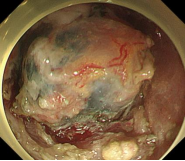

胃窦的腺癌 行ESD治疗

术中见较粗穿支血管,裸化后凝除,最终高效、安全的切除病灶。